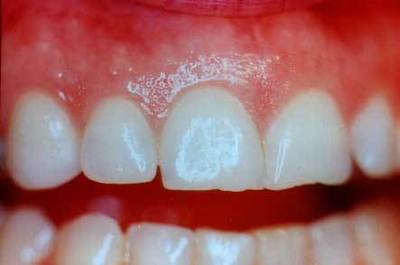

Рано возникающий

Данная форма включает в себя воспаления, возникающие у детей и подростков. Это может быть препубертатный пародонтит, ювенильный пародонтит или неопределенная болезнь пародонта. Чаще всего заболевание вызвано патогенными бактериями.

Фото 4. Рано возникающий пародонтит. Заболевание наблюдается у ребенка из-за несоблюдения гигиены полости рта.

Препубертатный

Такая форма пародонтита возникает, когда прорезываются постоянные зубы. Встречается достаточно редко и может быть как локализованная, так и генерализованная. Характеризуется ранним выпадением молочных зубов из-за нарушения прикрепления десны. Десневая ткань при этом воспаляется, появляется небольшой отек. Возможно появление кровоточащих трещин.

Ювенильный или юношеский

Встречается в основном у подростков в локализированной форме. Согласно статистике, чаще всего подвержены заболеванию именно девушки. Протекает пародонтит этого типа практически бессимптомно.

Возникает даже из-за небольшого количества налета. Причины появления пародонтита такой формы — грамотрицательные анаэробные бактерии. Заболевание приводит к вертикальной потере кости у первых моляров.

Нередко воспаление захватывает резцы. Дёсны при начале болезни краснеют, появляется несильный зуд.